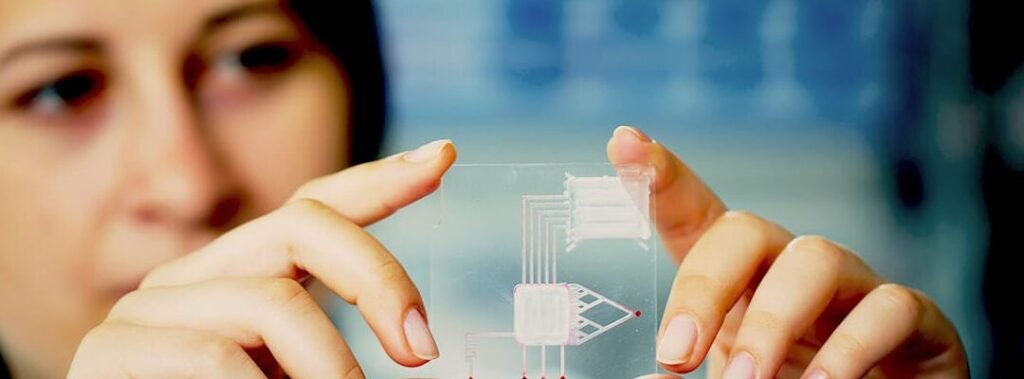

promete revolucionar la medicina al ofrecer un monitoreo preciso y mínimamente invasivo de la salud. Estos dispositivos,...